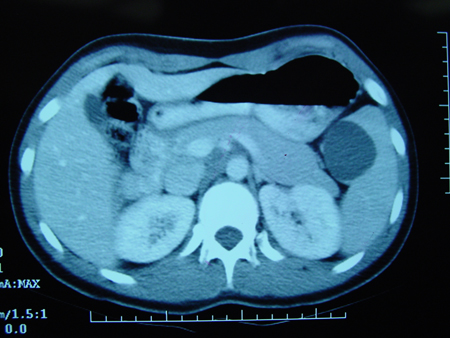

Больше - tomografia computadorizada (TC) de abdome e pelve:

apêndice dilatado, líquido livre, encarceramento mesentérico, ou apendicolito; abscesso ou flegmão consistente com apendicite perfurado